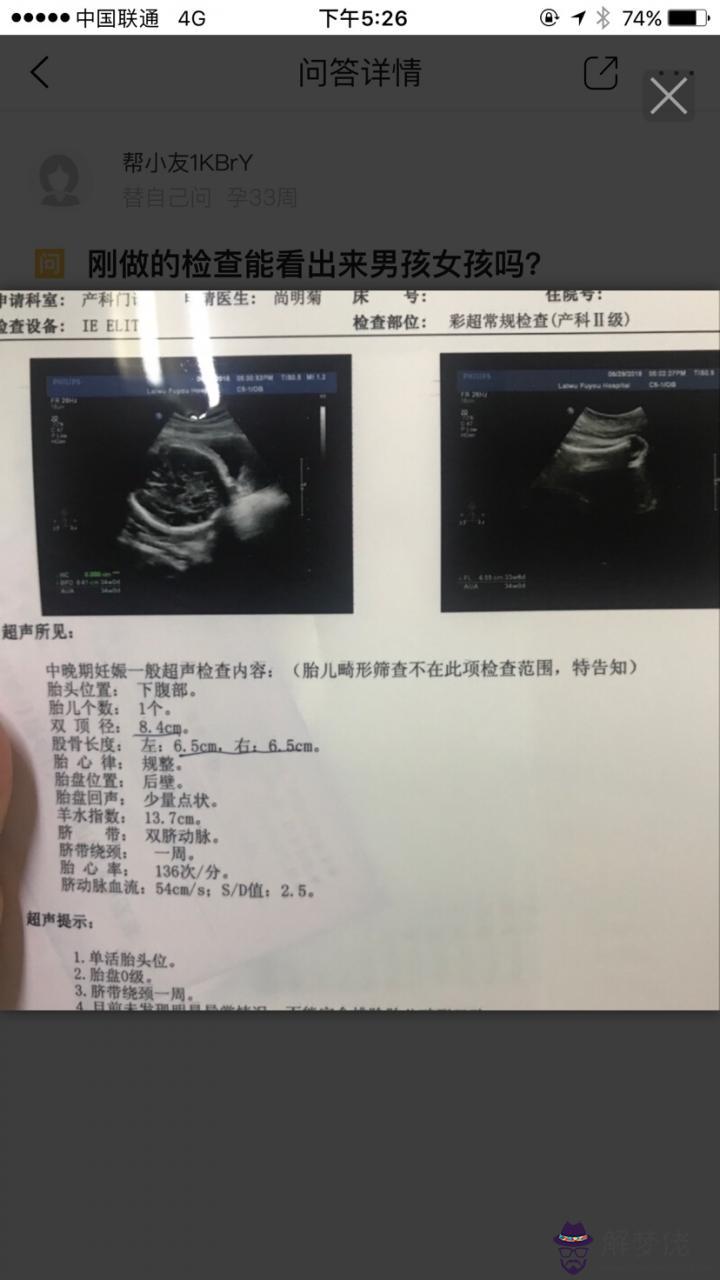

5、懷孕多久可以看出性別:怎樣從四維彩超的報告單的數據看出是男孩還是女孩?

四維彩超主要是用于檢查胎兒發育情況的輔助項目,通過此項檢查,可以了解胎兒在母體內各部位發育情況,如胎位,頭面部、臟器。神管、以及四肢發育情況,這個檢查項目多數在懷孕26-30周期間做。

這樣是看不出來的,只有在照的時候才可以看出來,但醫生是不會給你看的,你問也不會說的。現在禁止的,但是有的小醫院還是會給看的!但還是要給紅包

四維b聲辨別胎兒性別需要通過觀察來確定,目前我國的產前超聲檢查規范中胎兒是不在篩查范圍之內的,而且**也明令禁止做非醫學需要的胎兒性別鑒定。單純就b超報告單而言,報告上通常會有一張寶寶面部的三維圖,不會有的圖像或資料出現在報告上,所以無論是二維、三維或四維b超單都是無法分辨胎兒性別的。成都新華